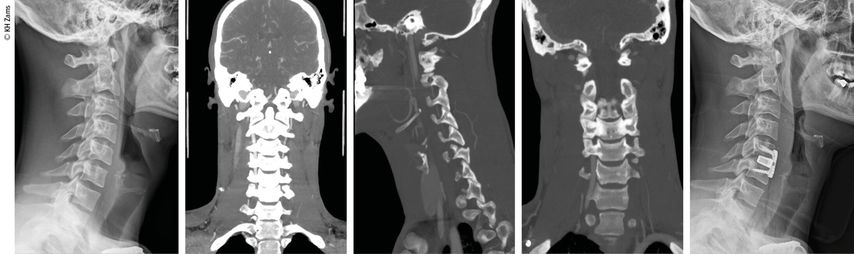

Vaskuläre Pathologien der Halswirbelsäule, insbesondere Dissektionen der A. carotis oder der A. vertebralis, sind potenziell lebensbedrohliche Zustände. Sie treten häufig infolge von stumpfen oder penetrierenden Traumata auf und sind klinisch oft schwer zu erkennen. Die frühzeitige multimodale Diagnostik und das adäquate interdisziplinäre Management sind von essenzieller Bedeutung für eine erfolgreiche Behandlung.

In der vorderen Halsregion liegt die A. carotis communis, diedem Aortenbogen (links) bzw. dem Truncus brachiocephalicus (rechts) entspringt. Sie teilt sich typischerweise auf Höhe des dritten bis vierten Halswirbels in die zwei wichtigsten Endäste für die Versorgung von Kopf und Hals. Bei dieser Gabelung befindet sich der Bulbus caroticus als Teil des sinuaortalen Systems. Etwas 2–3cm distal des Bulbus befindet sich die typische extrakranielle Lokalisation für Dissektionen. Die A. vertebralis entspringt in 90% der Fälle der Hinterwand der A. subclavia. Der Gefäßverlauf wird vom Ursprung der Arterie bis zur hinteren Schädelgrube unter anatomischen und klinischen Gesichtspunkten in vier Abschnitte unterteilt: